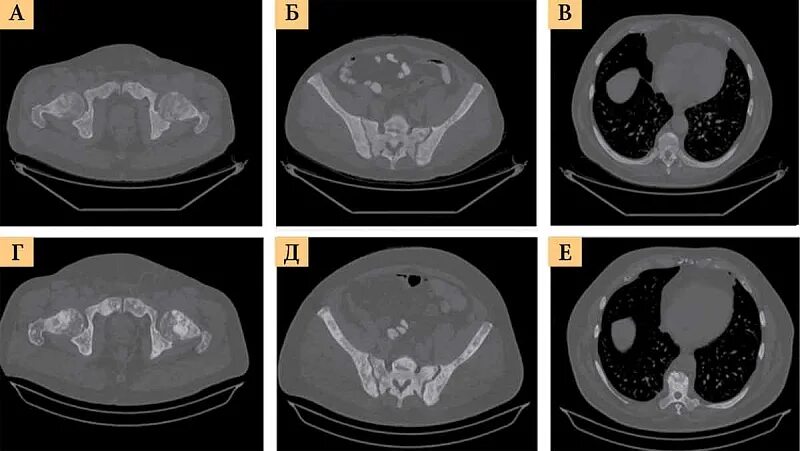

Метастазы в простате